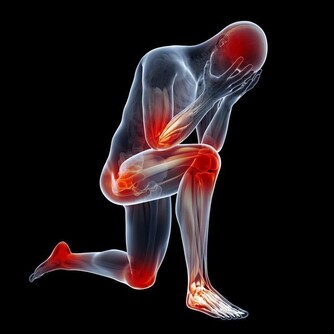

如果經常感覺到自己的嘴角有口瘡出現,而且容易全身疼痛,多半是某些重要的維生素缺乏了,特別是維生素D缺乏的時候應該高度重視。維生素D獲取充足能夠促進身體對鈣質的吸收,很多人全身疼痛,主要和鈣質缺乏有關,骨質疏鬆這種情況比較明顯,很多人就會感覺到全身產生疼痛感,甚至會有肌肉無力的感覺。

如果已經有這種現象,需要從飲食過程中獲取足夠的維生素D,平時還可以適當曬曬太陽,這樣可以促進身體對維生素D的合成,防止缺乏維生素D而出現全身疼痛表現。